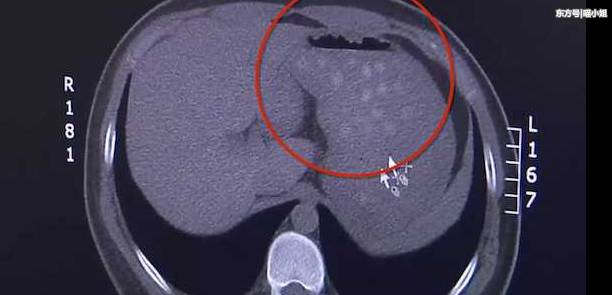

近日,大连的高中生小高上课的时候,突感腹部有些疼痛,甚至有些恶心,于是他便去医院做检查,还拍了腹部CT片。CT片子显示,小高的胃里出现了好多圆形的小白点儿,大概有三四十粒,并且小高的胃已经扩张了,胆囊也能明显看出增大了。据小高回忆,他当天吃了很多零食,还喝了两杯珍珠奶茶。通过小高的描述,医生断定这些圆形不易消化的物体就是珍珠奶茶里的“珍珠”。好在小高就医比较及时,经过治疗,症状很快得到了缓解。据其主治医师说,在他们医院,也接诊过多例因为吃了不易消化的食物,导致胆囊炎的患者,比如元宵、粽子等等,但这些食物一般不会在CT片上显影,这次珍珠奶茶里的“珍珠”显影如此明显,说明它难以消化的程度非常高。小编提醒,“珍珠”虽好吃,但要适量。